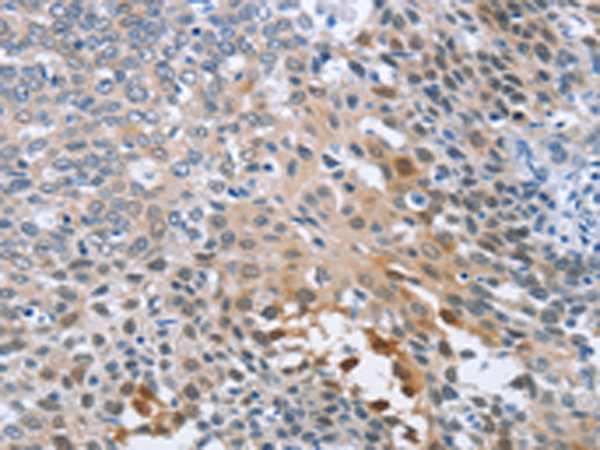

分类: 科研抗体货号: P08161别名: LB1; TMAP; se20-10应用: IHC反应种属: Human